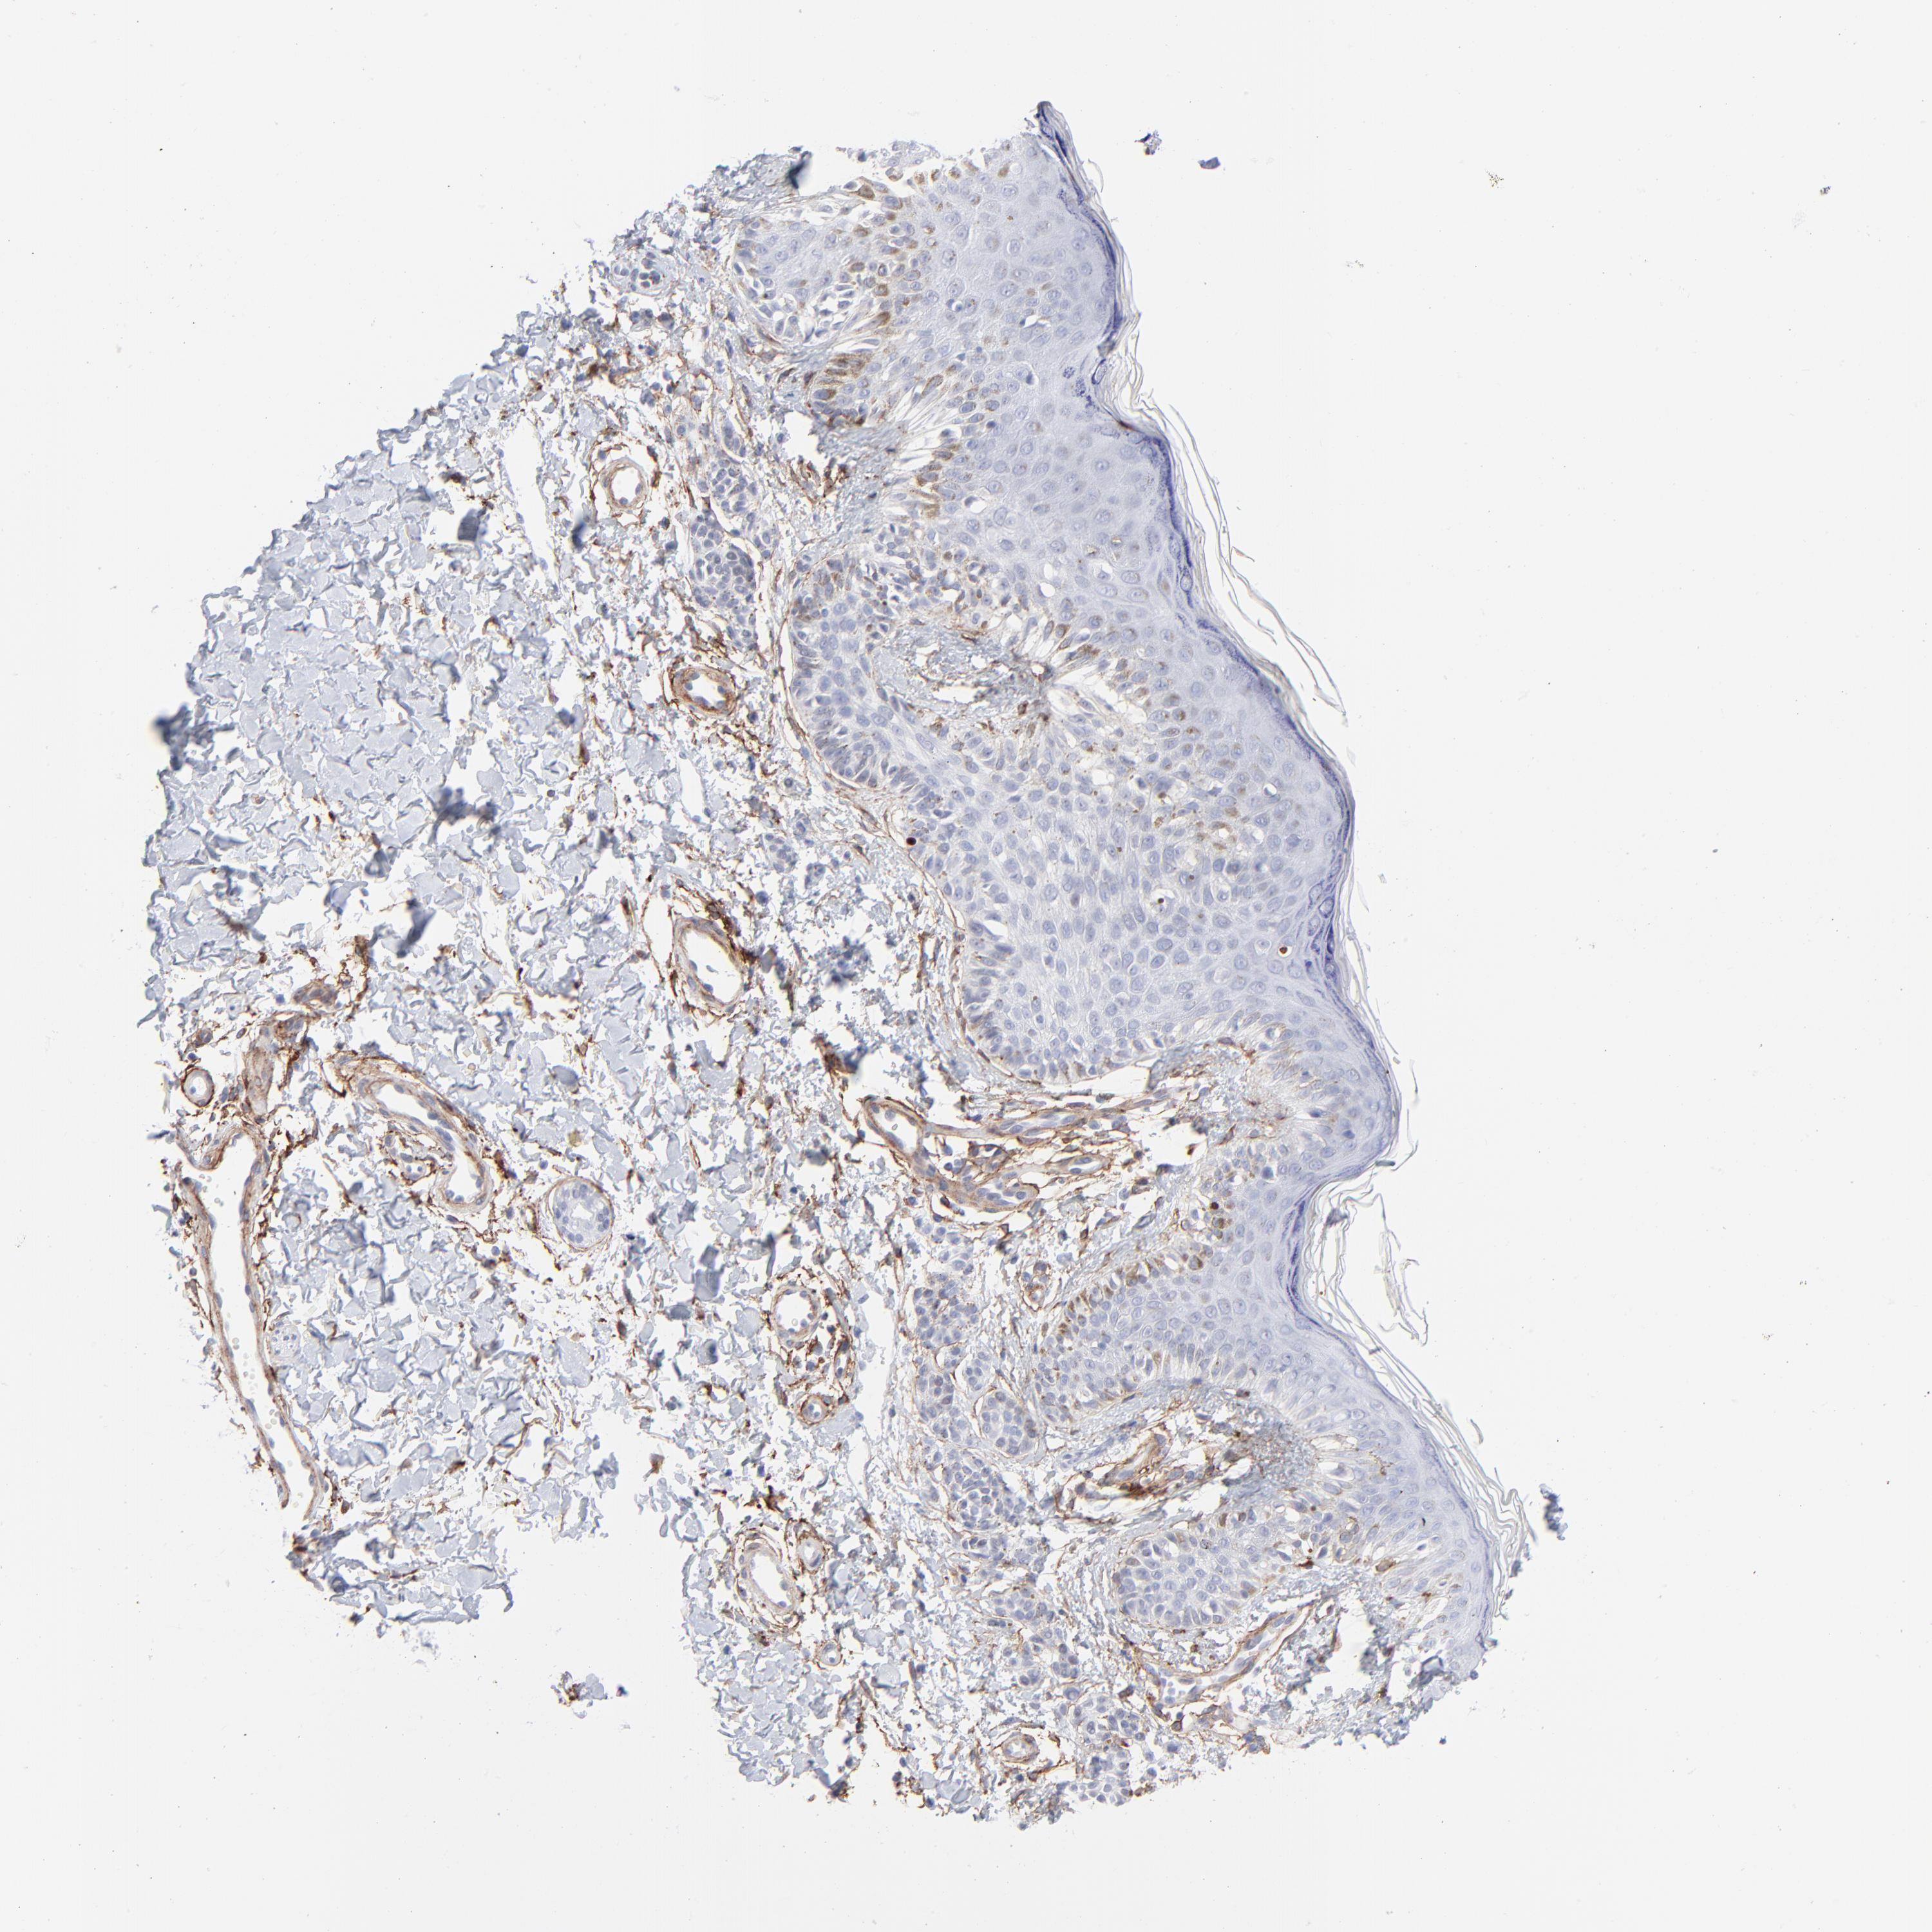

MELANOMA - Protein expressioni

A mouse-over function shows sample information and annotation data. Click on an image to view it in a full screen mode. Samples can be filtered based on level of antibody staining by selecting one or several of the following categories: high, medium, low and not detected. The assay and annotation is described here.

Note that samples used for immunohistochemistry by the Human Protein Atlas do not correspond to samples in the TCGA dataset.

Antibody stainingi

Antibody staining in the annotated cell types in the current human tissue is reported as not detected, low, medium, or high, based on conventional immunohistochemistry profiling in selected tissues. This score is based on the combination of the staining intensity and fraction of stained cells.

Each image is clickable and will lead to virtual microscopy that enables deeper exploration of all samples and also displays staining intensity scores, fraction scores and subcellular localization as well as patient and tissue information for each sample.

Antibody CAB003842

Antibody CAB018144

Malignant melanoma, NOS

Malignant melanoma, Metastatic site